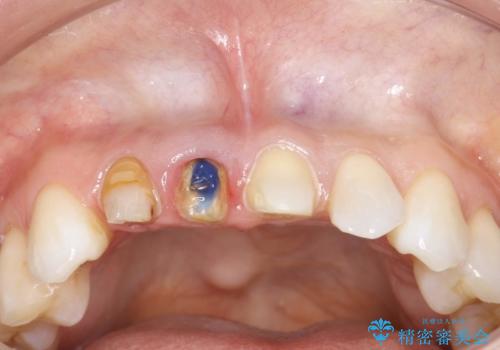

前歯がぐらぐらする 抜歯→ブリッジへ

古いかぶせ物は土台ごと歯から脱落してしまっており、歯の内面には複数の亀裂が入っている状態でした。残存歯質が非箔であることと、動揺の程度から、やむを得ず抜歯→ブリッジという方法を選択していただき、歯根挺出を用いることでなるべく前歯の骨の陥没を防ぎ、ブリッジを製作しました。

かぶせ物の種類:PFZ standard